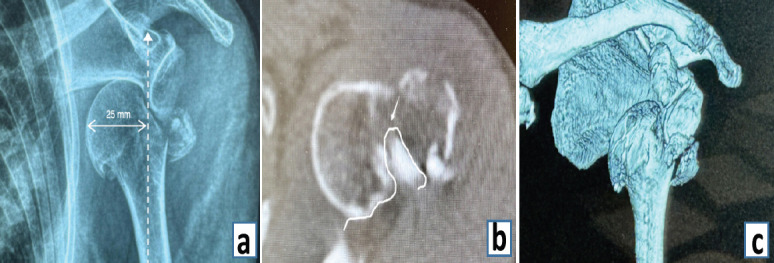

Case report: An 83-year-old Chinese female presented with left shoulder pain and restricted mobility after a ground-level fall. Physical examination revealed a squared shoulder deformity, deltoid muscle strength of 2/5, and sensory abnormalities in the axillary nerve territory. Radiographs confirmed anteroinferior humeral dislocation with comminuted greater tuberosity fracture. Closed reduction attempts failed twice. Three-dimensional.

Ct demonstrated: ① Hill-Sachs defect engaging the anterior glenoid rim; ② coronally split greater tuberosity fragment interposed in joint space; ③ 25 mm medial displacement of proximal humerus. The deltopectoral approach exposed the long head of biceps tendon traversing humeral head, forming complex interposition. Kirschner wire (K-wire) joystick technique was employed to disimpact osseous blocks. Tension band suturing combined with locking plate fixation was performed. Biceps tendon integrity was completely preserved. The post-operative course was uneventful, with satisfactory functional and radiographic outcomes and no recurrent dislocation during follow-up.